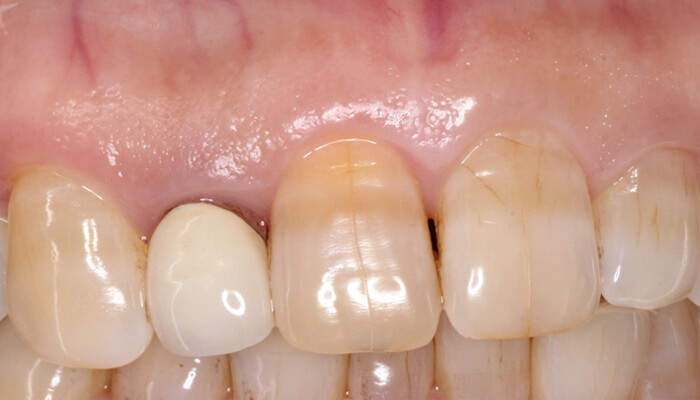

11. 術後半年での口腔内写真、根の先の瘻孔の再発もなく、傷口もほぼ目立ちません。歯ぐきもさがらず、被せものも変えなくて大丈夫でした。

9. 術前と、術後の歯ぐきの状態です。切開縫合の傷跡はほぼ目立ちません。

7. 術直後(抜糸時)と術後1年の経過観察時の比較です。切開の痕跡はほぼわかりません。